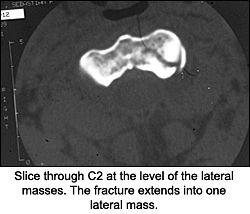

On the CT scan through the C1-2 vertebrae, note the fracture through the dens and the lateral mass of C2. (That was the depression we saw on the APOM of the lateral mass.) Should we look at the APOM view again?